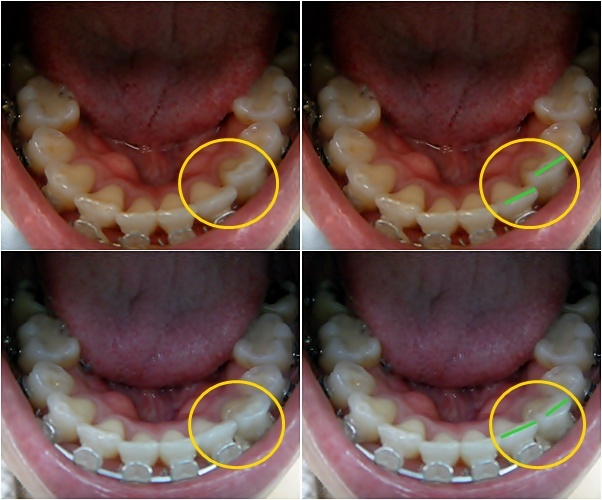

라인이 살짝 안 맞는 아래 앞니를 맞추기 위해 와이어를 구부리고 파워체인을 한바퀴 감아 당겨 주었어요~

그 결과~ 이렇게 전체적으로 U 라인이~ 짜자쟌~ ' ㅁ')b

제가 보기에는 완전 가지런해 보였었는데...!! orz

원장선생님께서 말씀해주시기 전까지는 라인이 안 맞는 줄 몰랐어요~ ㅠㅅㅠ

이렇게 미세한 부분까지 완벽하게 교정해 주시는 선생님 정말 감사합니다~ :D